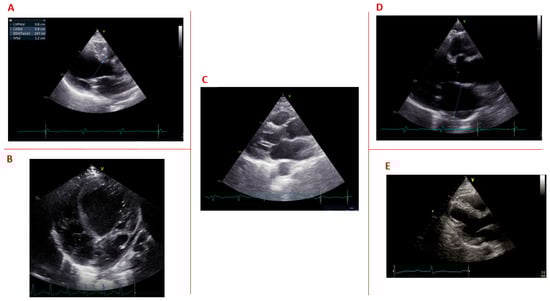

1.6. Structural Cardiac Abnormalities

| Bhakta [48] | 2003 | Based on a prospective multicenter registry | 382 | 42.2 ± 12.3 (17.9–77.8) | - | Structural cardiac abnormalities | Structural cardiac abnormalities determined with cardiac imaging included left ventricular hypertrophy (19.8%), left ventricular dilatation (18.6%), left ventricular systolic dysfunction (14.0%), mitral valve prolapse (13.7%), regional wall motion abnormality (11.2%) and left atrial dilatation (6.3%). |